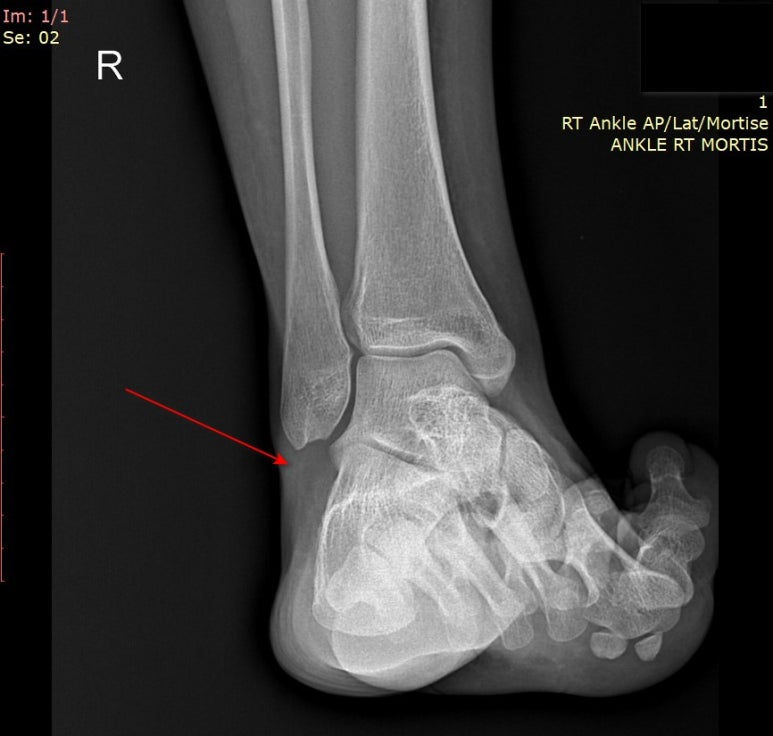

빨간 화살표친

발목 바깥쪽 뒤쪽이

불편하시다고요.

엑스레이로 인대가 보일까?

엑스레이상

인대가 늘어났다고 들으셨다며

영상 CD를 복사해오셨는데요.

어떤가요?

지금 여러분들 눈에는

인대의 정확한 경계가 보이시나요?

엑스레이에서는

인대 경계가 정확하게 보이지 않아요

X-ray에서는

인대손상을 정확하게 진단할 수는 없고

추정진단만 할 수 있는데요.

인대가 늘어나는 방향으로

발목을 밀어

두 뼈 사이 간격을 측정하면

인대가 완전히 찢어졌는지

의심할 수 있죠.